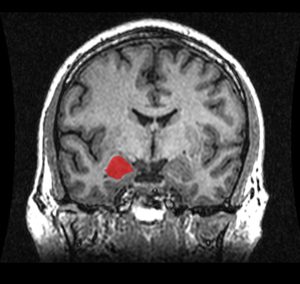

![]() موقع لوزة المخ في المخ البشري. | |

لوزة المخ amygdalaecorpus amygdaloideum؛ باللاتينية، من اللاتينية ἀμυγδαλή, amygdalē، 'almond', 'tonsil'[1])، مدرجة في تشريح گراي باسم nucleus amygdalæ، هي مجموعتين من النوى على شكل لوزة تقعان في المنطقة العميقة والوسطى داخل الفص الصدغي في المخ لدى الثدييات المتطورة، ومنها البشر.[2] أظهرت الأبحاث أن للوزة المخ دوراً أساسياً في معالجة الذاكرة، صنع القرار، وردود الفعل العاطفية، وتعتبر لوزة المخ جزءاً من الجهاز الحوفي.[3]

Frontal and side view of amygdala

Amygdala highlighted in green on coronal T1 MRI images